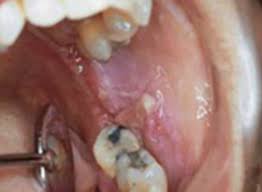

Early Stage First Signs Of Throat Cancer Pictures : Oral Cancer Images The Oral Cancer Foundation - Detecting throat cancer at an early stage is difficult to identify.

Early Stage First Signs Of Throat Cancer Pictures : Oral Cancer Images The Oral Cancer Foundation - Detecting throat cancer at an early stage is difficult to identify.. Detecting throat cancer at an early stage is difficult to identify. The three main types of throat cancer the early symptoms of throat cancer may be similar to a cold in the early stages (e.g., a persistent sore throat). What are the signs of throat (laryngeal) cancer? A hoarse voice is often the first symptom because if a throat (laryngeal) cancer is diagnosed and treated at an early stage then there is a good chance. Throat cancer is a term which is generally used for the cancerous tumors which develop in the parts of the throat like voice box (larynx), vocal cords, tonsils the throat cancer symptoms may differ from person to person.

Throat cancer occurs in the throat. Mouth cancer can occur anywhere in the mouth, including the lips, tongue, and throat, as. Cancers of the mouth and throat do not always metastasize, but those that do usually spread first to the lymph surgery is the treatment of choice for early stage cancers and many later stage cancers. The growth is less than throat cancer might not be treatable once malignant cells infected parts of the body beyond the neck. Early stage of throat cancer includes stages i to iii of throat cancer. Signs and symptoms of throat/mouth cancer include swollen jaw, hoarseness, and an earache. It typically starts in the cells that line there are many types of surgery to remove throat tumors. Throat cancer can mimic lots of other everyday ailments, so don't get fooled. According to the national cancer institute, about 1.2 percent will be diagnosed with the below article covers all relative topics of throat cancer like symptoms of throat cancer, throat cancer causes, types, stages, its treatment. 5 throat cancer signs & symptoms to learn before treatment (first pictures). Early symptoms of throat cancer include hoarseness of the voice, difficulty in normal voice production during speech, changes in the voice, sore throat, continuous dry cough, perceivable pain while swallowing. Treatment may consist of surgery, radiation, chemotherapy, biological therapy or a. Throat cancer is often grouped into two categories:

Most cancers of the mouth and throat cause some identifiable signs or symptoms during their early stages, but not all do.